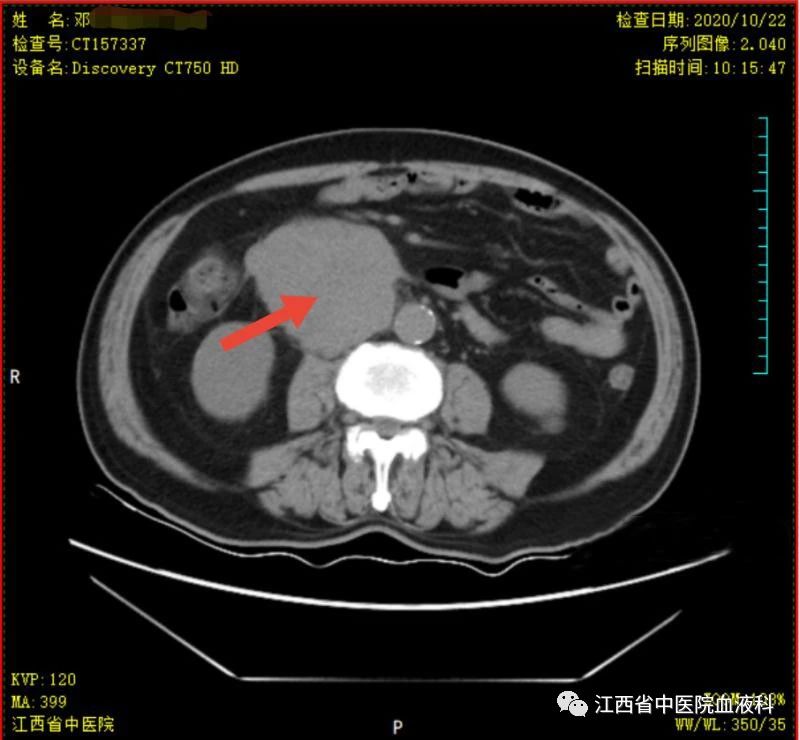

2020年10月中旬邓大爷在家人的陪同下来我科就诊,全腹部增强CT提示:右侧睾丸切除术后复查:1.腹膜后(胰头后下方)、双侧肾上腺区团块状异常强化影。2.肝左内叶上段小囊肿,双肾小囊肿,较前相仿。3.右侧腹股沟前方、皮下条索、小片影,境界不清,较前减小,拟为术后改变。4.右下腹腔少许钙化淋巴结,较前相仿。因病情危急,考虑邓大爷高龄、体能差、窦性心动过缓(平均心率50次/分)心脏功能差等情况,经讨论于2020-10-24起第一次行减剂量方案R-miniCHOP(利妥昔单抗700mg d0、环磷酰胺700mg d1、多柔比星40mg d1、长春瑞滨20mg d1、地塞米松10mg d1-5)方案。第一次化疗后评估病情,腹腔瘤体缩小了2/3,取得了很好的治疗效果,可邓大爷心脏却亮起了红灯,经过了积极护心等支持治疗后,大爷心脏功能有所恢复。遂于2020-11-19、2020-12-10行2次R-miniCOP方案(去除了具有心脏毒性的多柔比星),三次化疗结束后予评估病情,提示腹腔包块明显缩小,淋巴瘤病情有所好转。